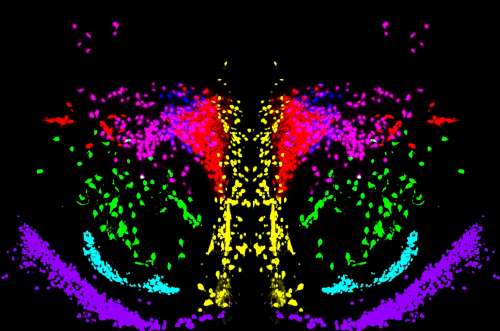

Tal y como señala Sandra Jurado, “gracias a las novedosas técnicas de reconstrucción 3D de circuitos neuronales se podrán identificar las potenciales alteraciones del sistema de oxitocina en regiones concretas del cerebro de animales modelo. Una vez que se hayan identificado las regiones más afectadas podremos dirigir nuestras herramientas moleculares para intentar compensar el déficit de oxitocina en estas zonas concretas”.